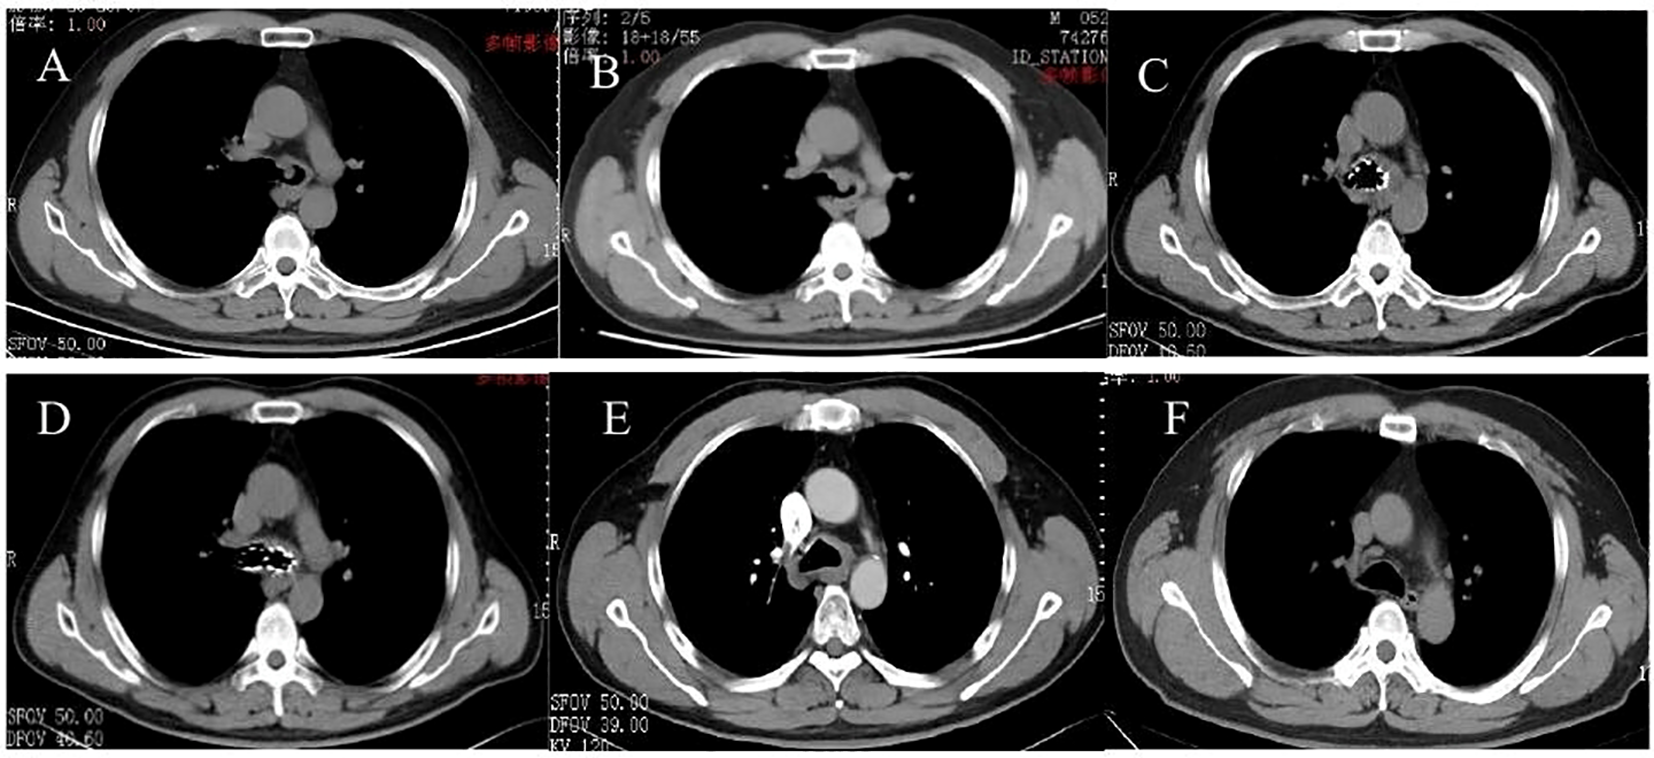

Figure 2

CT pictures. (A) 5 January 2017, tracheal adenoid cystic carcinoma (TACC) on the left side of the lower trachea near the carina. (B) 5 January 2019, TACC recurred. (C, D) 18 April 2019, 125I seed stent implanting. (E) 21 June 2019, after the 125I seed stent removing. (F) 17 August 2023, the main bronchus more than 4 years after removing the stent.

The findings were confirmed by chest CT (Figure 2A). To reduce the risk of surgical bleeding, bronchial arteriography and embolization were performed before bronchial interventional surgery due to the abundant blood supply to the neoplasm. The patient underwent intratracheal tumor resection under general anesthesia. Three pieces of tissue were removed with a snare, and the mass was excised using an argon knife and cryotherapy was administered. Based on microscopic morphology, immune markers, and pathological examination results, the patient was diagnosed with adenoid cystic carcinoma. Bronchoscopy results were reexamined 3 days after the operation; the lumen was unobstructed, and the left main bronchus was clear after resection of the visible neoplasm, and the mucosa was intact within the visible range (Figure 1B). After discharge, he was advised to return for a review in 3–6 months; however, he did not follow the doctor’s recommendations. He was admitted to the hospital again due to recurrent cough, expectoration, and wheezing for 1 month, approximately 2 years later, on 5 January 2019. Results of chest CT performed after admission showed occupation of the tracheal and left main bronchus spaces, similar to the previous results (compared with January 2017) (Figure 2B). A reexamination of bronchoscopy results on 8 January 2019 revealed obstruction of the left main bronchus due to tumor recurrence; the bronchoscope could not pass through, and the blood supply on the surface of the new organism was obvious (Figure 1C). Due to tumor recurrence after 2 years of interventional bronchoscopy, the patient underwent airway neovascularization and 125I seed airway stent implantation on 17 January 2019.

The patient tolerated the surgery well and had no complications, such as chest pain, persistent cough, hemoptysis, mediastinal emphysema, fistula formation, or secondary pulmonary infection. Bronchoscopy reexamination was performed 3 days later to evaluate the expansion status, position, and whether there were seeds falling off of the stent. Bronchoscopy revealed that the Y-shaped stent was completely attached to the wall, and the seeds remained intact without any displacement. Mucosa congestion and edema were evident within the visible range, and viscous secretions were visible. Sputum was aspirated, revealing a long strip of white necrotic tissue in the lower part of the stent, and was sent for examination. On 18 April 2019, the patient underwent a follow-up chest CT scan, which showed an unobstructed lumen and slight thickening of the left main bronchus wall (Figures 2C, D). A reexamination of bronchoscopy results showed that the position of the left stent was fixed, without movement and deformation. There were increased viscous secretions and sputum scabs in the stent, with the mucosa intact in the remaining visible range. Five months postoperatively, on 19 June 2019, 125I seed stent removal was performed under general anesthesia. The procedure was as follows: Under general anesthesia, an electronic bronchoscope was inserted through a laryngeal mask. The Y-shaped stents in the left and right main bronchi adhered well. The position was stable with no displacement, although granulation tissue was visible in the lower part of the left main bronchus stent (Figure 1E). The laryngeal mask was removed, and a STORZ rigid bronchoscope was inserted using extraction forceps placed through it. The seed stent was completely removed, with all 24 seeds intact and without any displacement. The seed stent was placed in a radiation-proof lead box. A postoperative follow-up chest CT scan on 21 June 2019 revealed thickening of the left wall of the lower trachea whereas the bronchial lumen remained unobstructed (Figure 2E). During the follow-up review in October 2019, July 2021, and August 2023, the patient showed no clinical symptoms such as cough and wheezing. On 17 August 2023, a CT scan showed reduced thickening of the left wall of the lower trachea, with no obvious thickening of the left main bronchial wall (Figure 2F). Bronchoscopy results revealed that the mucous membrane of the lower tracheal segment and the lateral wall of the left main bronchus was white before the seed stent, with no new lesions, and the mucous membrane was intact in the visible range (Figure 1F). The patient was followed up by telephone for 5 years post-seed stent implantation and intracavitary radiotherapy. The patient had no tumor recurrence or clinical symptoms, achieving an 8-year survival. The chronological progression of the entire case is shown in Figure 3.